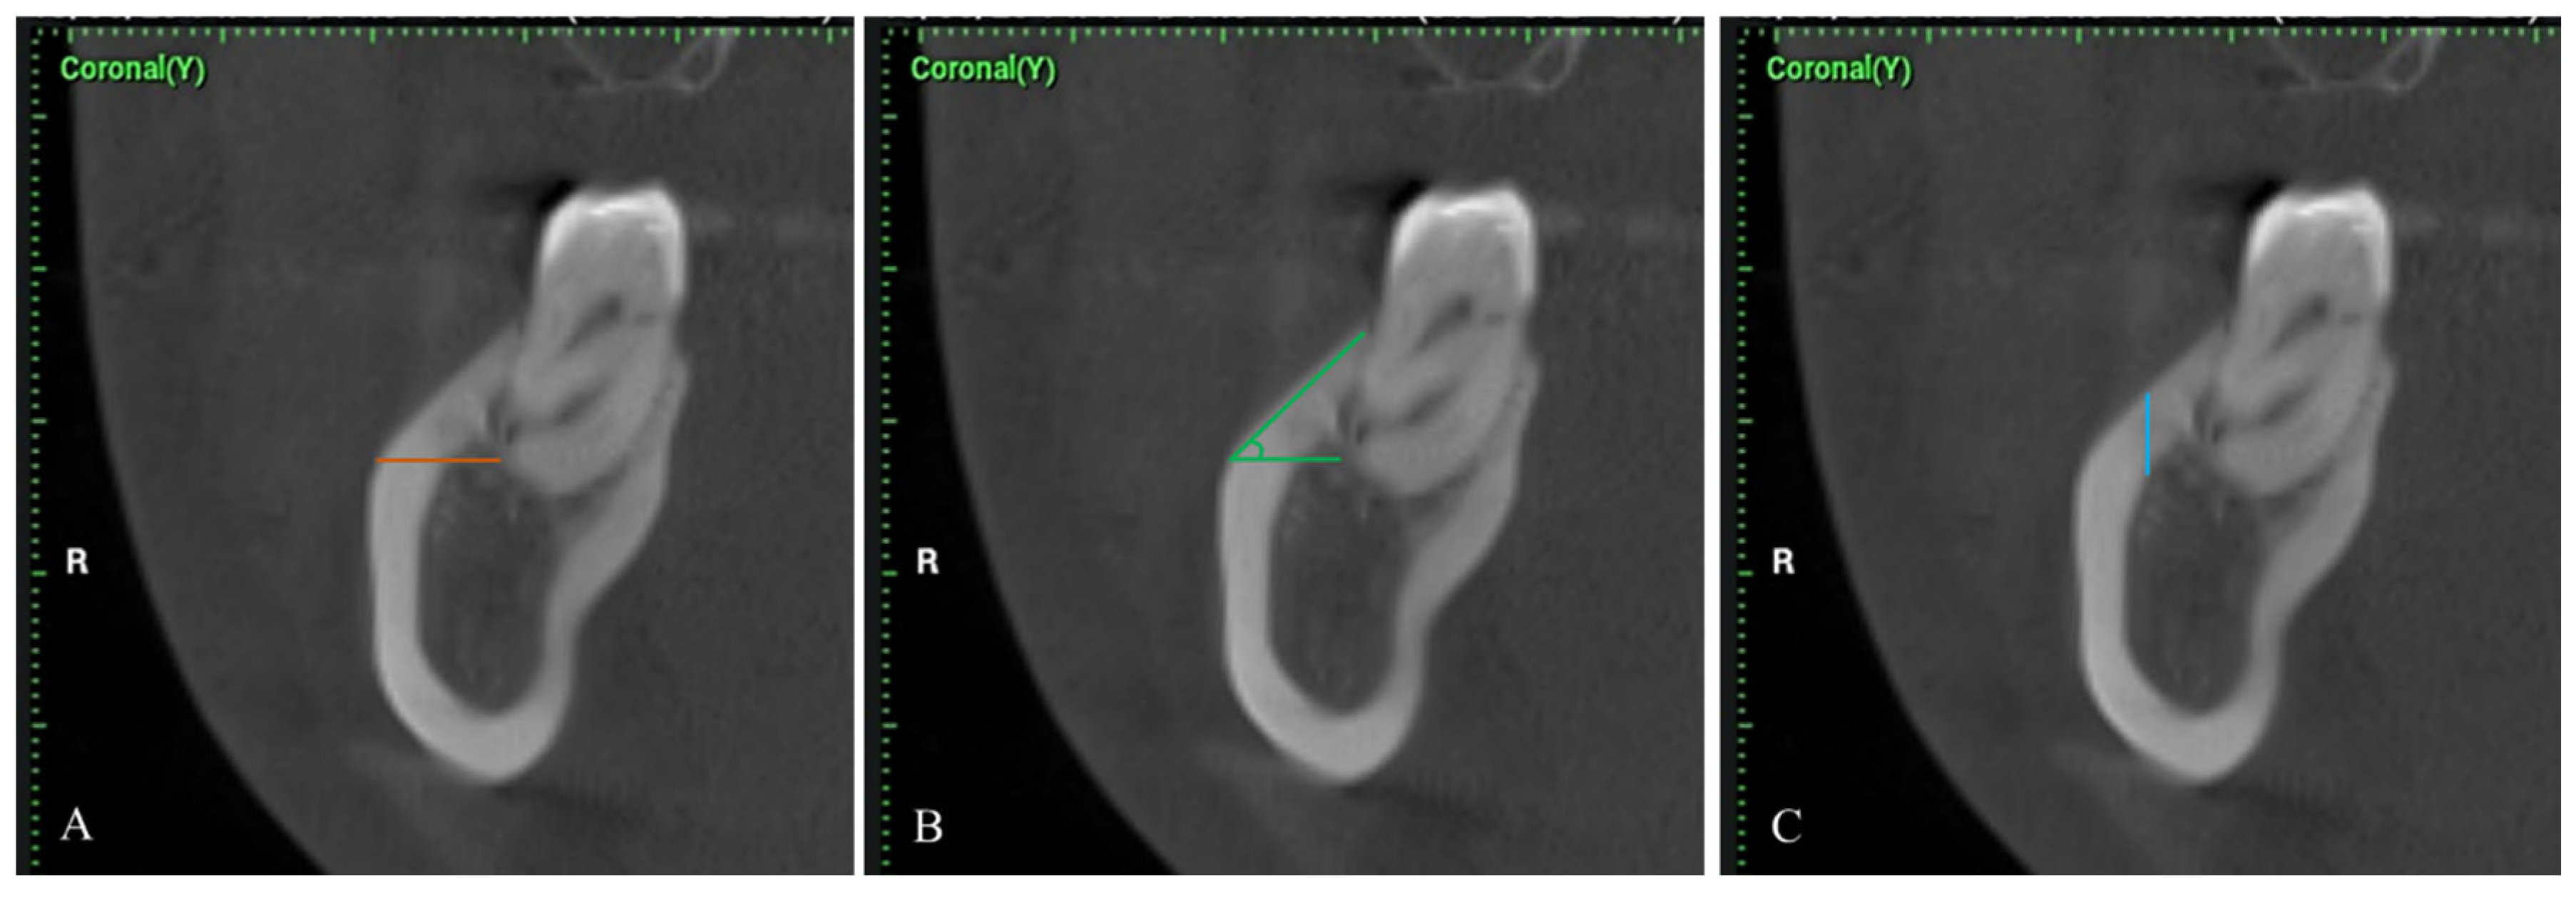

2. Materials and Methods